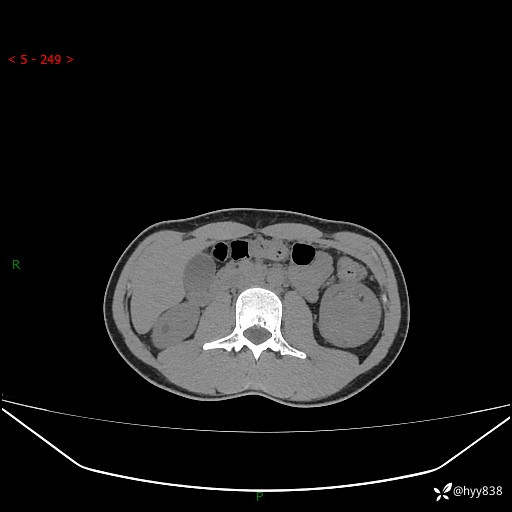

年轻男性,发现左肾占位1天。“非好病例”我不发,误诊率高---(有结果)

现病史:患者昨日中午进食后出现明显腹痛,腹泻,在我院急诊科行补液及对症治疗,双肾输尿管彩超提示左肾占位(5.2*4.3cm),平素无明显腰痛,无再发肉眼血尿等情况,现为求处理左肾占位,遂来我院,门诊以左肾占位收治入院。 患者起病以来,精神、食欲、睡眠尚可,大便可,小便如上,体力体重无明显下降。

双肾CT平扫+增强(三期)